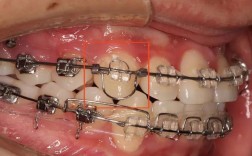

🦷 4. 传统唇侧矫治器配合口外力(高位头帽、J钩)或颌间牵引

- 原理: 在牙齿的唇侧面(靠近嘴唇的面)粘托槽,通过在弓丝上弯制压低曲(如欧米曲、T曲、垂直曲),配合高位头帽(牵引钩挂在需要压低的牙齿托槽的牵引钩上)或J钩(从口外弓挂在需要压低的牙齿上),施加垂直向压低力,有时也可利用颌间牵引(如III类牵引)间接产生压低效果(但主要作用是改变颌间关系)。

- 应用: 在种植体支抗普及之前是主要方法,现在常作为辅助手段或用于特定病例,J钩主要用于压低个别前牙。